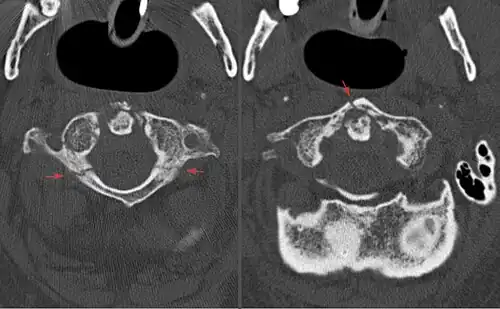

Axial CT scan showing a Jefferson fracture.

A Jefferson fracture is a bone fracture of the anterior and posterior arches of the C1 vertebra,[1] though it may also appear as a three- or two-part fracture. The fracture may result from an axial load on the back of the head or hyperextension of the neck (e.g. caused by diving), causing a posterior break, and may be accompanied by a break in other parts of the cervical spine.[1]